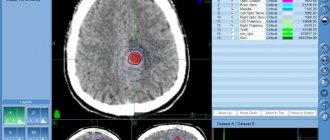

Безоперационное лечение астроцитомы — КиберНожом

Такой вид опухоли мозга, как астроцитома, является наиболее распространенным среди новообразований центральной нервной системы